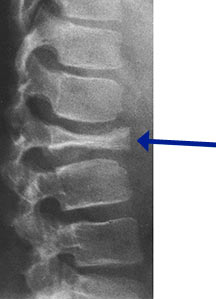

- May arise from any bone and any site within a bone (epiphyseal, metaphyseal, diaphyseal)

- Radiographically variable appearance: may appear benign (geographic) or malignant (permeative or moth eaten)